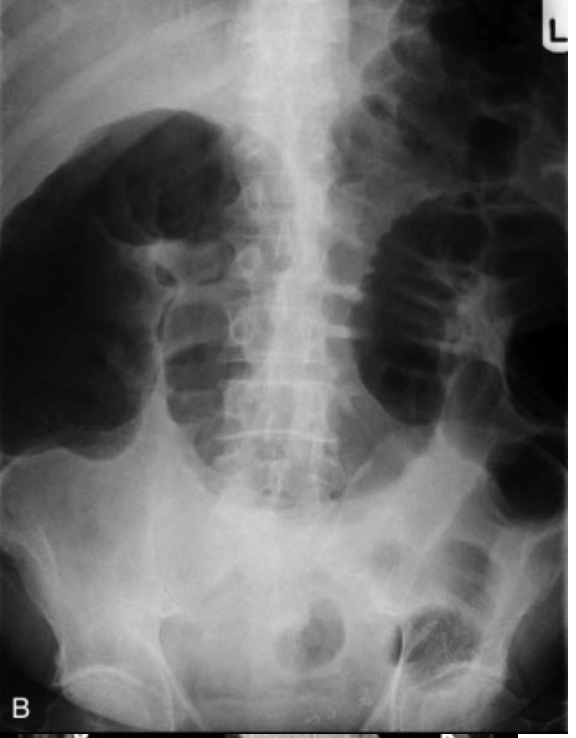

What is pictured here?